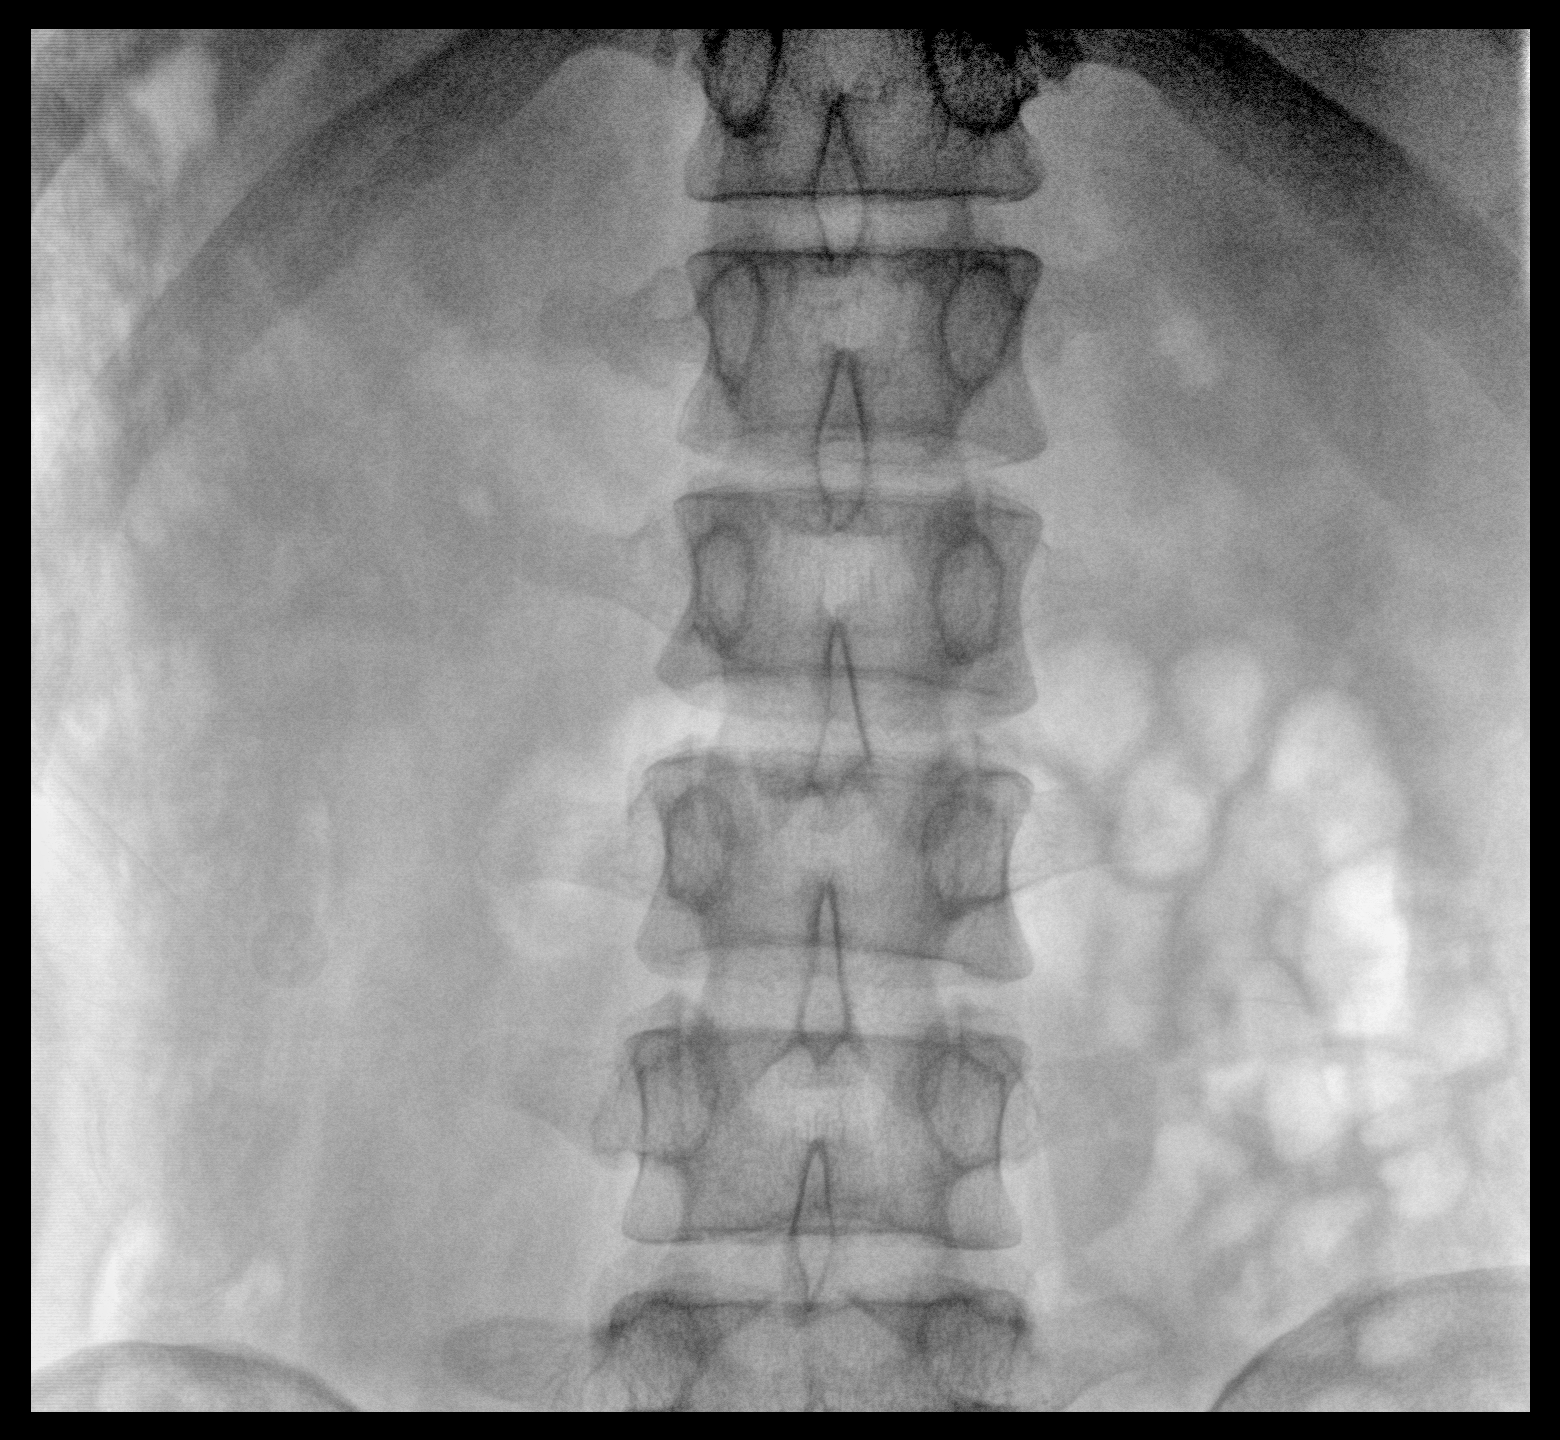

大尺寸動態(tài)平板探測器,高DQE、低噪聲、圖像清晰。采用多分辨率圖像增強(qiáng)處理技術(shù),不同部位不同圖像處理算法,滿足客戶多樣化的需求。

采用智能變頻脈沖透視技術(shù),優(yōu)化圖像質(zhì)量的同時降低輻射劑量,呵護(hù)醫(yī)患健康